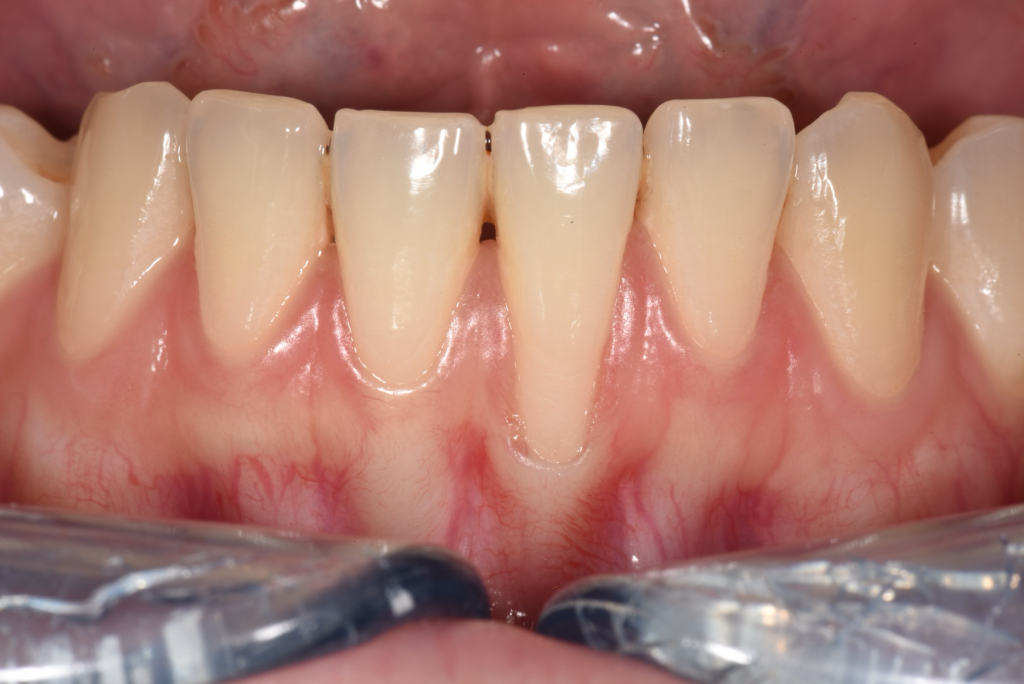

How do I know if I have receding gums?

– Your tooth may look “longer”

– The gum line looks uneven

– You may notice some exposure of the tooth root, which is of a different colour (usually darker/more yellowish)